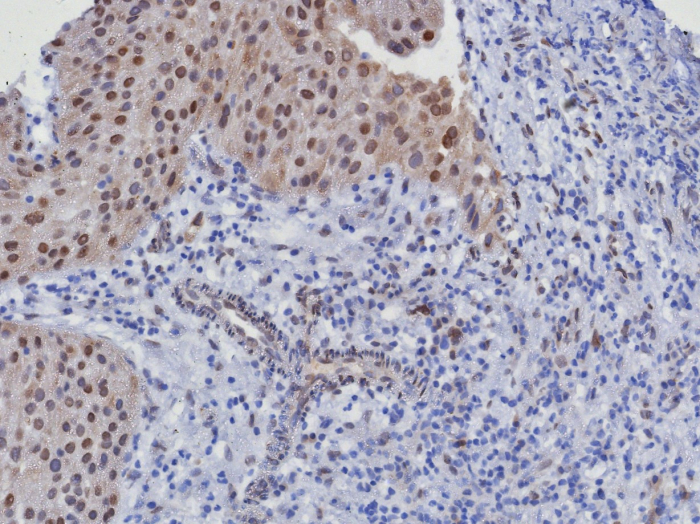

Formulation: Purified Ab WITHOUT BSA and Azide at 1.0mg/ml. Cellular Localization: Nucleus. Cytoplasm. Positive Control: MCF7, HEK293T, cervical carcinoma and liposarcomas., Human urothelial carcinoma, HeLa. Chromosome Location: 12q14.1. Protein Function: Ser/Thr-kinase component of cyclin D-CDK4 (DC) complexes that phosphorylate and inhibit members of the retinoblastoma (RB) protein family including RB1 and regulate the cell-cycle during G(1)/S transition. Phosphorylation of RB1 allows dissociation of the transcription factor E2F from the RB/E2F complexes and the subsequent transcription of E2F target genes which are responsible for the progression through the G(1) phase. Hypophosphorylates RB1 in early G(1) phase. Cyclin D-CDK4 complexes are major integrators of various mitogenenic and antimitogenic signals. Also phosphorylates SMAD3 in a cell-cycle-dependent manner and represses its transcriptional activity. Component of the ternary complex, cyclin D/CDK4/CDKN1B, required for nuclear translocation and activity of the cyclin D-CDK4 complex [The Uniprot Consortium]

| Application: | IHC, WB |